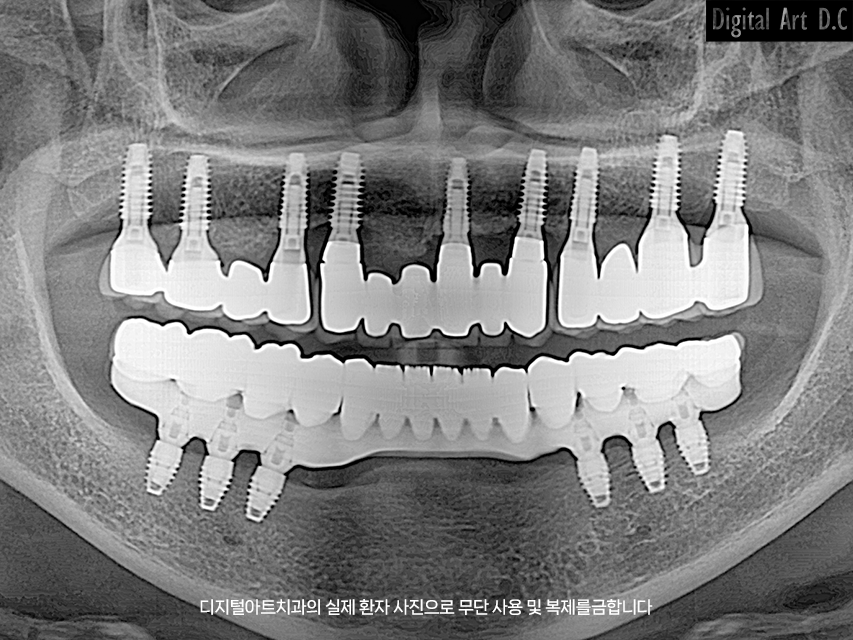

부산전체임플란트는 상악 또는 하악 전체 치아가 상실된 경우, 일정 개수의 임플란트를 식립하여 고정형 보철물을 연결하는 시술입니다. 틀니와 달리 고정형이기 때문에 음식 씹는 기능 회복과 심미적 만족도가 높습니다.

- All-on-4 / All-on-6 방식: 4~6개의 임플란트로 전체 보철물을 지지

- 개별 식립 방식: 치아마다 임플란트를 식립 (비용 높음)

- 하이브리드 보철 방식: 고정과 탈착식이 결합된 형태